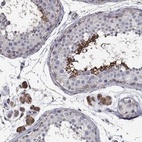

Immunohistochemical staining of human testis shows strong cytoplasmic positivity in cells in seminiferous ducts and Leydig cells.